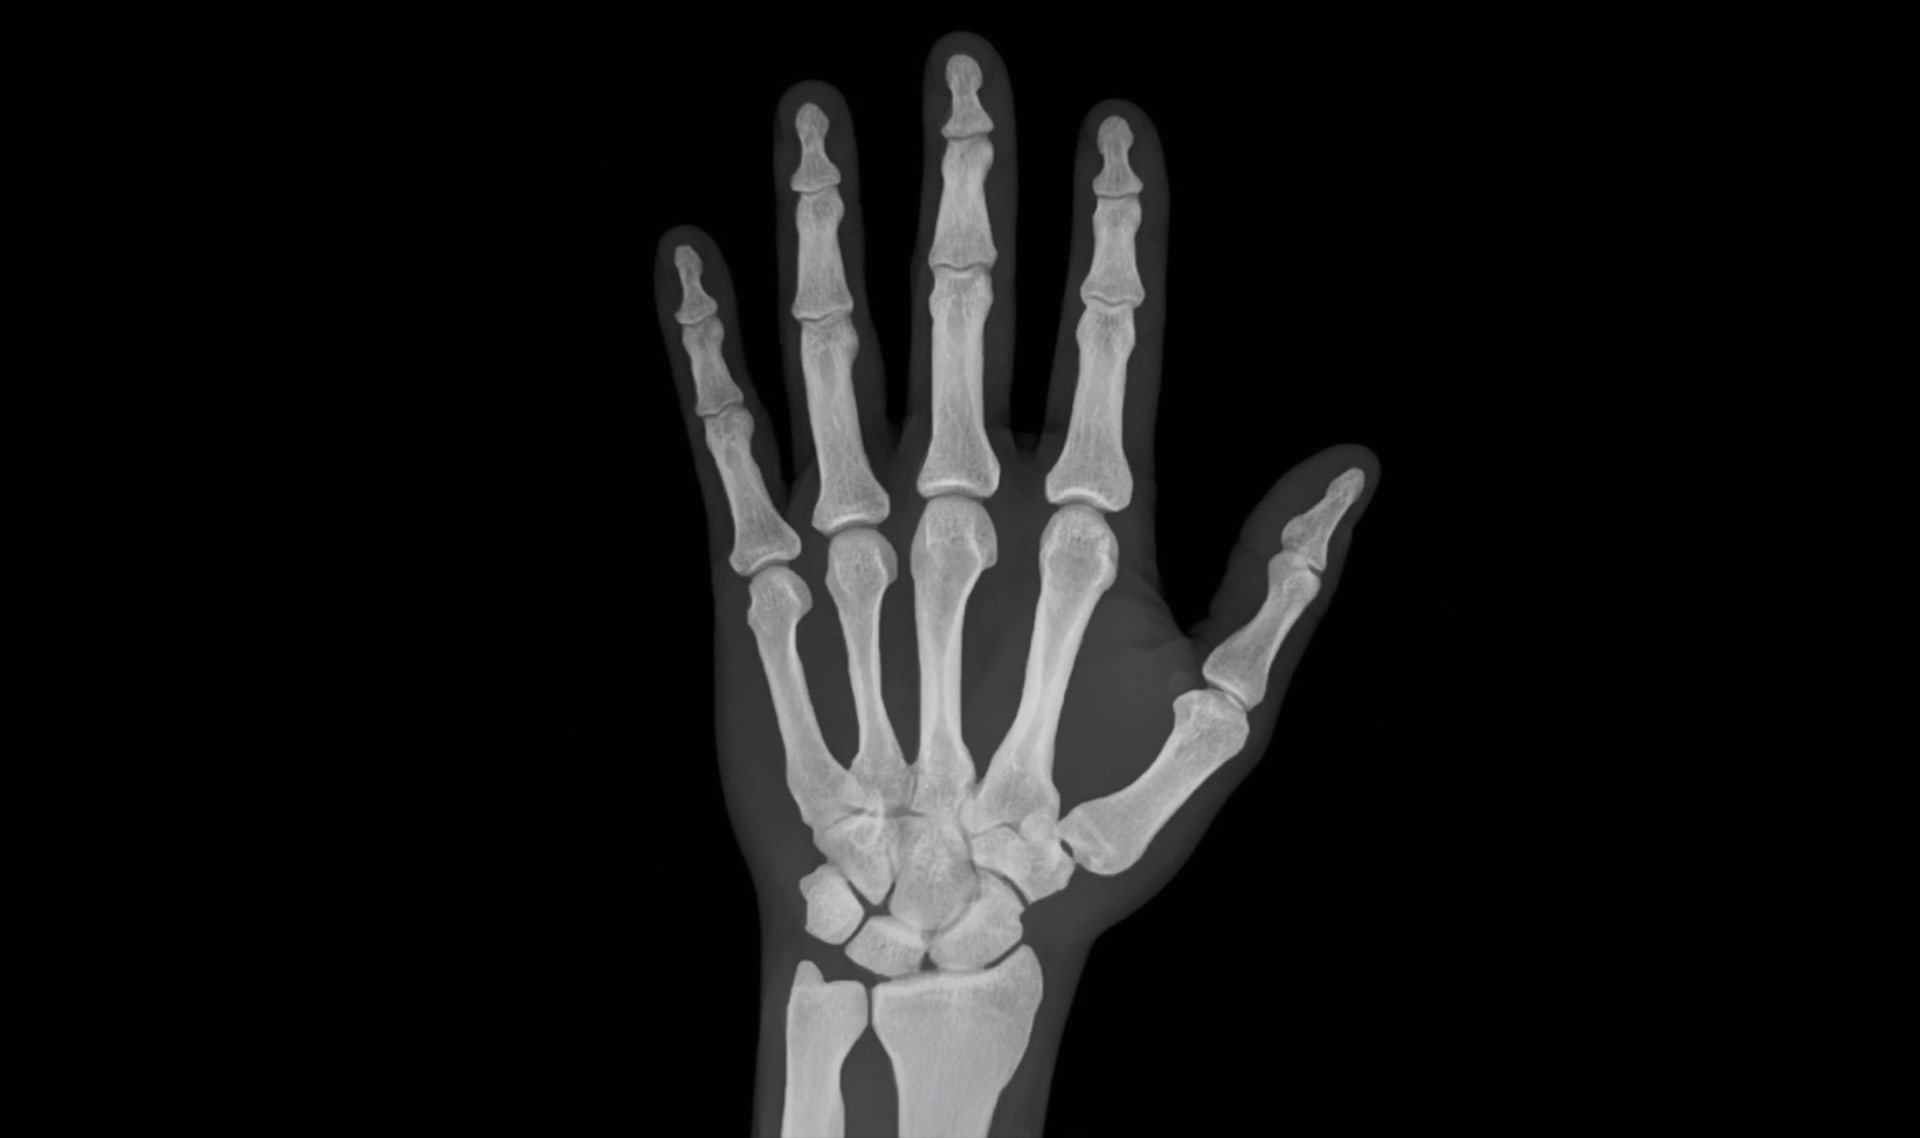

hand x-ray by Noah Weiss